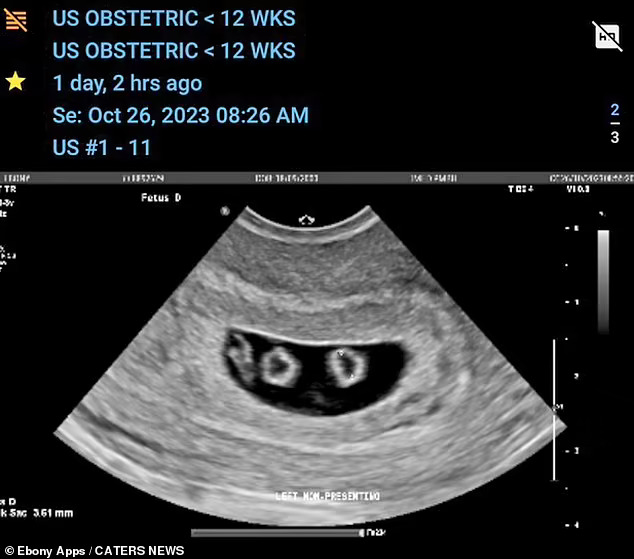

„Отидовме на нашиот прв ултразвук очекувајќи само едно бебе, а потоа ни рекоа дека се близнаци“, рече таа.

„Потоа, на нашето второ скенирање, ни беше кажано дека имаме четворки кои беа две групи идентични близнаци“.

Бременоста на идната мајка е поретка од четворократна бременост, бидејќи таа носи две групи идентични близнаци.